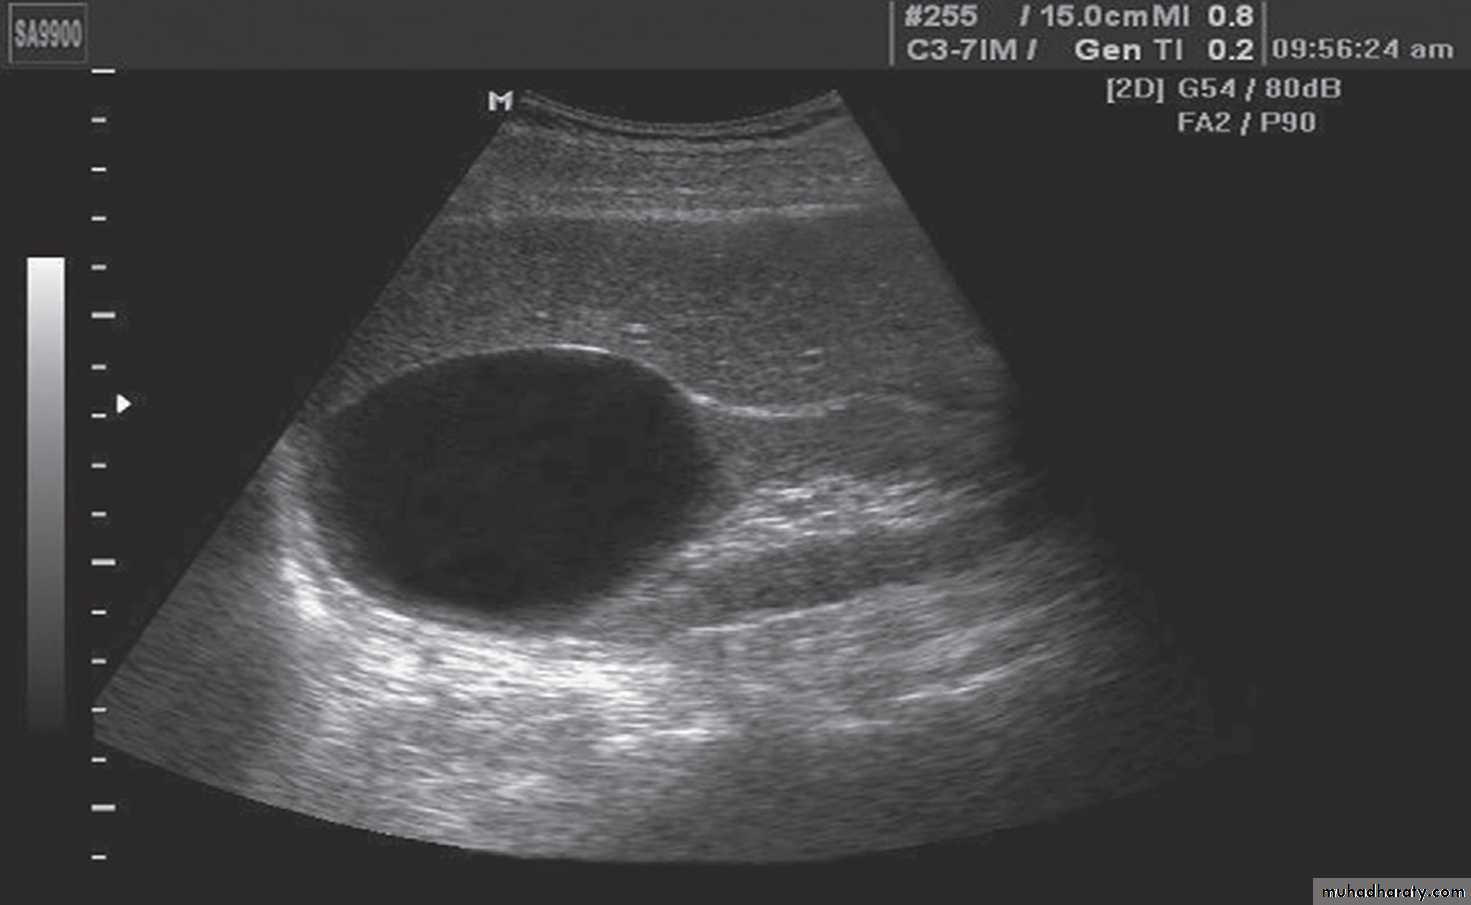

SIMPLE RENALCYSTS(U/S)

To diagnose a benign simple cyst on ultrasonography, it should

(1) have no internal echoes,(2) have a sharply defined, thin, smooth wall,

(3) spherical or oval.

When these criteria are not met, CT with contrast enhancement must be performed

Simple renal cysts are the most common cystic lesions found in the human kidney.Clinical Features:

they are asymptomatic and discovered incidentally on ultrasonography, CT. However, cysts can produce an abdominal mass or pain, hematuria and hypertension .